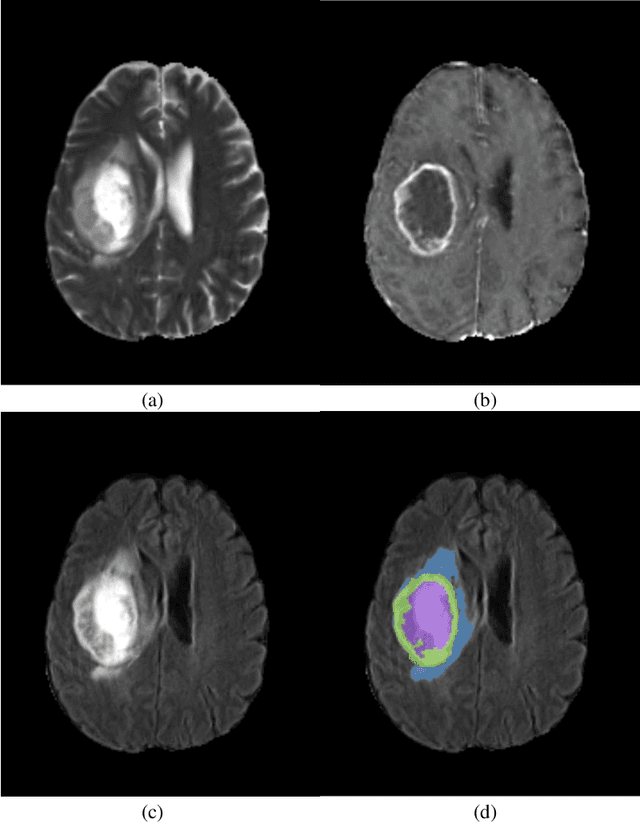

Abstract:Automatic segmentation is essential for the brain tumor diagnosis, disease prognosis, and follow-up therapy of patients with gliomas. Still, accurate detection of gliomas and their sub-regions in multimodal MRI is very challenging due to the variety of scanners and imaging protocols. Over the last years, the BraTS Challenge has provided a large number of multi-institutional MRI scans as a benchmark for glioma segmentation algorithms. This paper describes our contribution to the BraTS 2022 Continuous Evaluation challenge. We propose a new ensemble of multiple deep learning frameworks namely, DeepSeg, nnU-Net, and DeepSCAN for automatic glioma boundaries detection in pre-operative MRI. It is worth noting that our ensemble models took first place in the final evaluation on the BraTS testing dataset with Dice scores of 0.9294, 0.8788, and 0.8803, and Hausdorf distance of 5.23, 13.54, and 12.05, for the whole tumor, tumor core, and enhancing tumor, respectively. Furthermore, the proposed ensemble method ranked first in the final ranking on another unseen test dataset, namely Sub-Saharan Africa dataset, achieving mean Dice scores of 0.9737, 0.9593, and 0.9022, and HD95 of 2.66, 1.72, 3.32 for the whole tumor, tumor core, and enhancing tumor, respectively. The docker image for the winning submission is publicly available at (https://hub.docker.com/r/razeineldin/camed22).

Abstract:Glioblastomas are the most aggressive fast-growing primary brain cancer which originate in the glial cells of the brain. Accurate identification of the malignant brain tumor and its sub-regions is still one of the most challenging problems in medical image segmentation. The Brain Tumor Segmentation Challenge (BraTS) has been a popular benchmark for automatic brain glioblastomas segmentation algorithms since its initiation. In this year, BraTS 2021 challenge provides the largest multi-parametric (mpMRI) dataset of 2,000 pre-operative patients. In this paper, we propose a new aggregation of two deep learning frameworks namely, DeepSeg and nnU-Net for automatic glioblastoma recognition in pre-operative mpMRI. Our ensemble method obtains Dice similarity scores of 92.00, 87.33, and 84.10 and Hausdorff Distances of 3.81, 8.91, and 16.02 for the enhancing tumor, tumor core, and whole tumor regions, respectively, on the BraTS 2021 validation set, ranking us among the top ten teams. These experimental findings provide evidence that it can be readily applied clinically and thereby aiding in the brain cancer prognosis, therapy planning, and therapy response monitoring. A docker image for reproducing our segmentation results is available online at (https://hub.docker.com/r/razeineldin/deepseg21).

Abstract:Purpose: Gliomas are the most common and aggressive type of brain tumors due to their infiltrative nature and rapid progression. The process of distinguishing tumor boundaries from healthy cells is still a challenging task in the clinical routine. Fluid-Attenuated Inversion Recovery (FLAIR) MRI modality can provide the physician with information about tumor infiltration. Therefore, this paper proposes a new generic deep learning architecture; namely DeepSeg for fully automated detection and segmentation of the brain lesion using FLAIR MRI data. Methods: The developed DeepSeg is a modular decoupling framework. It consists of two connected core parts based on an encoding and decoding relationship. The encoder part is a convolutional neural network (CNN) responsible for spatial information extraction. The resulting semantic map is inserted into the decoder part to get the full resolution probability map. Based on modified U-Net architecture, different CNN models such as Residual Neural Network (ResNet), Dense Convolutional Network (DenseNet), and NASNet have been utilized in this study. Results: The proposed deep learning architectures have been successfully tested and evaluated on-line based on MRI datasets of Brain Tumor Segmentation (BraTS 2019) challenge, including s336 cases as training data and 125 cases for validation data. The dice and Hausdorff distance scores of obtained segmentation results are about 0.81 to 0.84 and 9.8 to 19.7 correspondingly. Conclusion: This study showed successful feasibility and comparative performance of applying different deep learning models in a new DeepSeg framework for automated brain tumor segmentation in FLAIR MR images. The proposed DeepSeg is open-source and freely available at https://github.com/razeineldin/DeepSeg/.